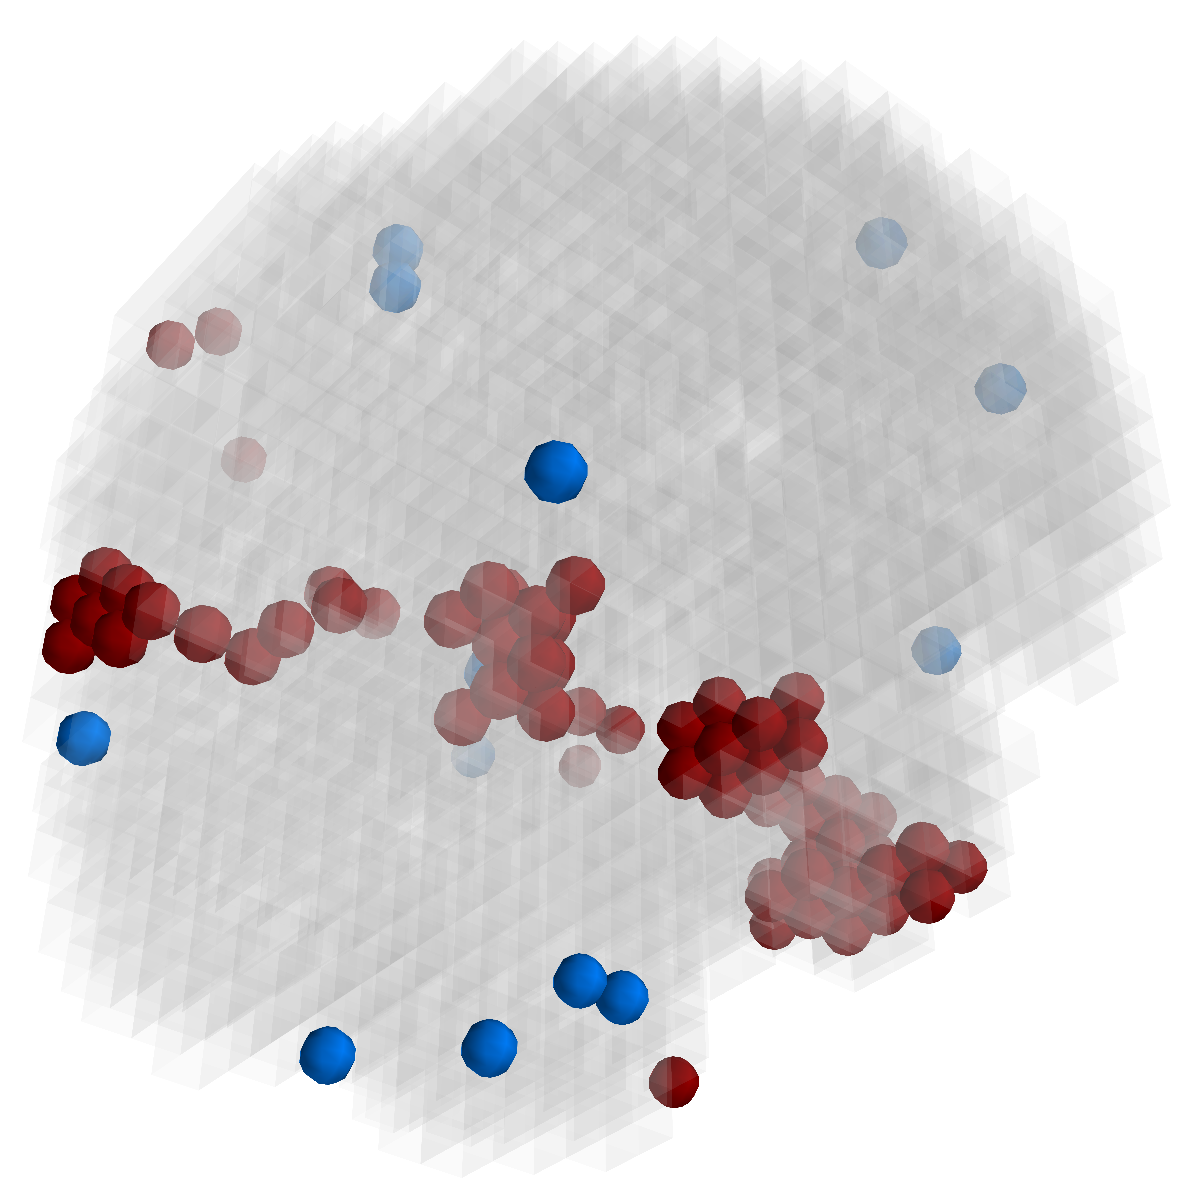

Figure 3: Stability of selected voxels across different folds of the cross-validation. The results of 5 different folds are shown in (a)-(e). The voxels with positive β𝛽\beta are in brown, negative ones are in blue. The common/overlapped voxels selected in all 10 folds are shown in green (f). The top row illustrates voxels selected by the lasso model, the mid row illustrates those of GFL and the bottom row shows those of n2superscript𝑛2n^{2}GFL.

Feature Stability. In Figure 3, we show the selected voxels across different folds of CV333Here, parameters were determined by accuracy. Similar results were observed using parameters producing same level of sparsity.. As shown, the selected voxels by lasso vary much across different folds, whereas the selected voxels by GFL are more stable. However, by assuming the positive correlation between the features and the disease labels in n2superscript𝑛2n^{2}GFL, we further increase the stability. To quantitatively evaluate the stability gain, we denote the variables of the k𝑘kth fold of CV as 𝜷(k)𝜷𝑘\boldsymbol{\beta}(k). We introduce two measurements here. In (?), the Estimation Stability (ES) is proposed to measure the stability of the estimation

where ##\# is the number of elements in a set. In Tab. 3, both measurements quantitatively suggest n2superscript𝑛2n^{2}GFL obtains much more stable voxels due to the consideration of the correlation between the features and the disease labels 444We notice that, in (?), the stability is computed using the top 50 positive voxels because these voxels are believe to be the most atrophied ones. By computing the stability of all non-zero voxels, the mDC of GFL drops around 30%percent3030\%. This clearly shows that the instability is caused largely by the undesirable voxels that disagree with the correlation prior (those scattered blue voxels in the mid row)..